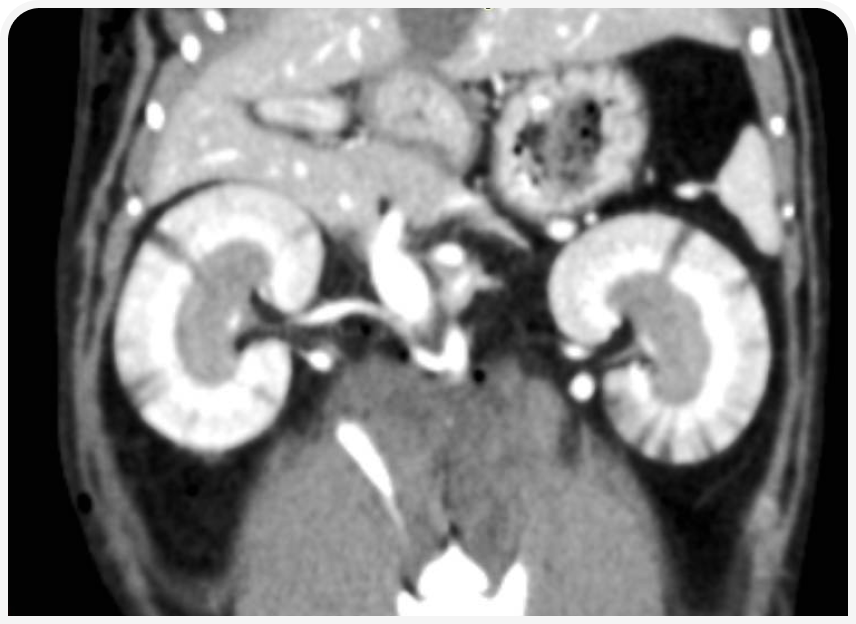

КТ-ангиография – наглядный метод диагностики, который может быть использован для демонстрации расположения тромба. По КТ-ангиографии оценивают дефект заполнения артериального сосуда контрастным веществом (рис. 7).

Помимо расположения самого тромба на КТ, необходимо исследовать другие ткани и органы на наличие дефектов контрастирования. В нашей практике у животных с ТЭК мы обнаруживали мелкие инфаркты коркового слоя почек, которые до этого не удавалось выявить на УЗИ (рис. 8), и сегментарный дефект распределения контраста в паренхиме селезенки.